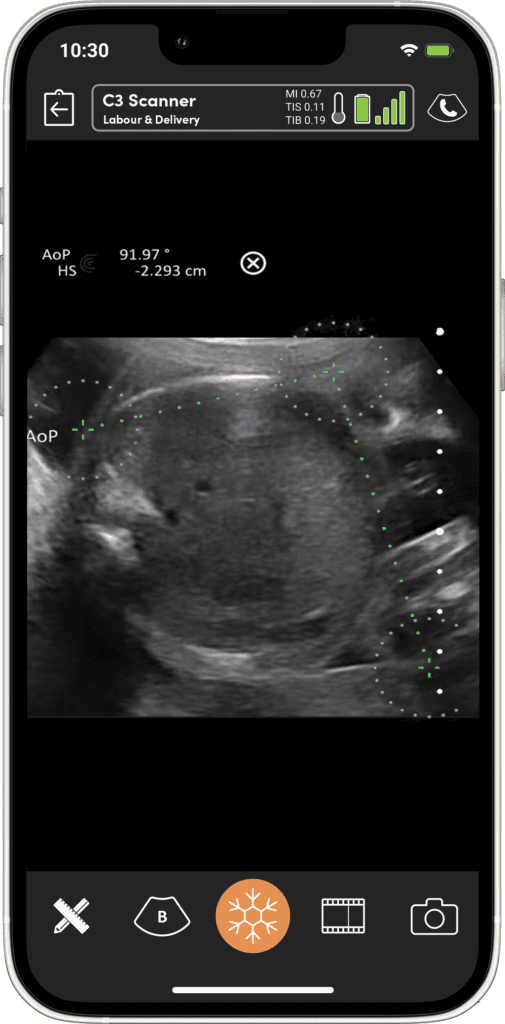

Imagerie Obstétricale Optimisée

I feel more confident with my ultrasound exams since I’ve started using OB AI. I love how the AI makes the app light up when things are perfectly lined up – I can see this really helping both seasoned clinicians and those who are starting their ultrasound journey.